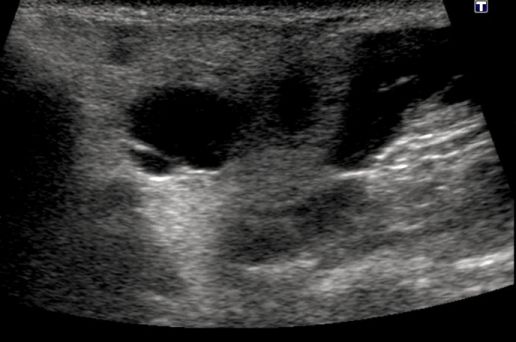

Ultrasound of the neck was ordered to determine the composition of the swelling. Findings included bilateral parotid masses identified as enlarged parotid glands with multiple 2- to 3-cm cysts present within the glandular tissue (Figures 1-3).

Figure 2.